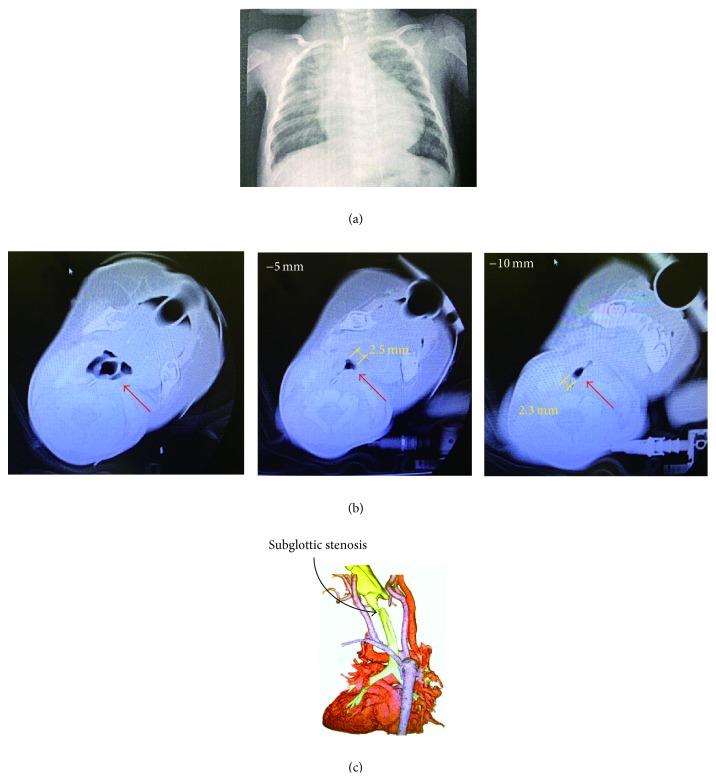

A 4-month-old female infant who weighed 3.57 kg with severe subglottic stenosis underwent tracheostomy under extracorporeal cardiopulmonary support. First, we set up extracorporeal cardiopulmonary support to the infant and then successfully intubated an endotracheal tube with a 2.5 mm inner diameter before tracheostomy by otolaryngologists. Extracorporeal cardiopulmonary support is an alternative for maintenance of oxygenation in difficult airway management in infants.

一名体重3.57千克的4个月大女婴患有严重的声门下狭窄,在体外心肺支持下接受了气管造口术。首先,我们为该婴儿建立了体外心肺支持,然后耳鼻喉科医生在气管造口术前成功插入了一根内径为2.5毫米的气管内导管。体外心肺支持是婴儿困难气道管理中维持氧合的一种替代方法。